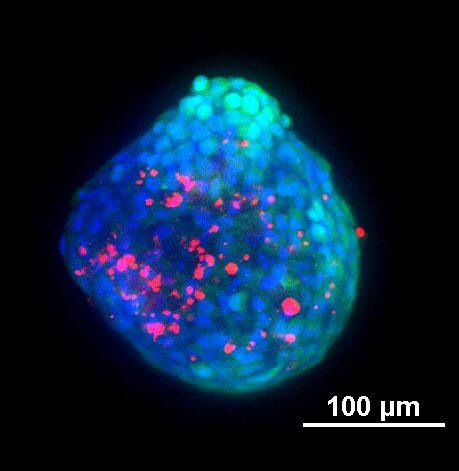

为了生成 3D 球体,将 NCI-H460 细胞(源自非小细胞肺癌)以两种不同的密度接种在超低吸附培养板中:3×103 个细胞/孔或 700 个细胞/孔。在直径分别达到约 400-500 或 150-200 um 后,用细胞毒素剂处理球体 6 天。通过使用钙黄绿素 AM 和碘化丙啶 (PI) 的活/死染色来观察和评估药物的效果。钙黄绿素 AM 是一种细胞渗透性染料,用于测定细胞活性。非荧光钙黄绿素 AM 在活细胞中被细胞内酯酶水解后转化为(绿色)荧光钙黄绿素。PI 是一种红色荧光核染色剂,通常用于检测死亡细胞,因为它不能进入完整的活细胞。最后,使用 Hoechst 染料将细胞核染成蓝色。

我们采用 CrestOptics X-Light V3 转盘共聚焦结合 Prime BSI 相机(Photometrics,像素尺寸 6.5 um)进行采集。我们比较了使用 20 倍空气物镜(CFI Plan Apo Lambda,尼康,0.7 NA 和 1mm WD)和 25 倍硅油物镜(CFI Plan Apo Lambda S,尼康,1.05 NA 和 0.55 mm WD)进行的采集。在图 A 中,我们展示了从总共 150 um 的 Z 堆栈中获得的最大强度投影 (MIP) 图像;特别是,使用 20 倍空气物镜和 25 倍硅油物镜获得了相同的球体。图 B 显示了使用两种物镜获得的 3D 球体同一区域的放大。

使用 20 倍空气物镜和使用 25 倍硅油物镜获得的图像之间的比较(图 A、B 和 C)突出了基于生物应用的透镜选择的重要性。从 20 倍到 25 倍的转换导致分辨率提高(基于 25 倍的 NA 大于 20 倍 NA),这当然会影响图像质量,并且还会导致光折射减少。事实上,浸油通过用更高折射率的介质代替透镜和盖玻片之间的空气间隙,大大提高了显微镜的分辨率,从而减少了光的折射。

在 3D 成像中,样品的折射率与其浸没介质的折射率相匹配对于深层组织观察至关重要。硅酮浸油非常适合透过厚厚的生物样本进行成像;它与细胞和封固剂的折射率非常吻合,与使用普通 20 倍空气物镜获得的图像相比,减少了球面像差,产生了更亮、分辨率更高的图像。

图 A:使用 20 倍空气物镜(顶部)和 25 倍硅油物镜(底部)获得的肿瘤球体 Z 堆栈的最大密度投影 (MIP)。活细胞用钙黄绿素(绿色)标记,死细胞用 PI(红色)标记。细胞核用 Hoechst(蓝色)染色。比例尺:100 um。这些图像是使用 CrestOptics X-Light V3 转盘获取的。